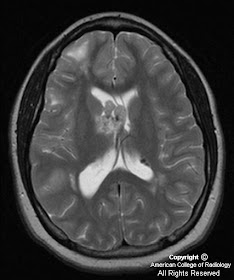

Axial T2-weighted and FLAIR MR images demonstrate a mass near the foramen of Monro with heterogenous, somewhat hyperintense signal compared to white matter. Intense homogeneous enhancement is seen on contrast-enhanced axial and coronal T1 weighted images. Subependymal nodules are seen along the lateral ventricles. Multiple foci of increased signal are seen on FLAIR images in the subcortical regions representing parenchymal tubers.

Diagnosis: Subependymal giant cell astrocytoma (SEGA)

Hamartomatous brain lesions include cortical tubers, white matter heterotopias, subependymal nodules, and the subependymal giant cell astrocytoma. Histologically, cortical tubers, white matter lesions, and subependymal nodules are identical lesions composed of disordered neurons, glia, and giant cells mostly of the astrocyte type, only differing in size and location. Subependymal nodules are usually easily identified with CT due to frequent calcification (>90%) and usually do not enhance thus helping to distinguish, but not entirely exclude a SEGA from a subependymal nodule. Cortical tubers are less likely to calcify and appear as low attenuation lesions at CT, demonstrate increased signal intensity on T2-W images, and rarely enhance. White matter lesions are seen as curvilinear or straight bands of increased T2 signal extending from the ventricles. SEGAs are characterized by slow growth and a benign biological behavior (WHO grade I), likely arising from the degeneration of subependymal nodules. On CT, SEGAs are iso-to slightly hypoattenuating intraventriuclar masses located near the foramen of Monro, with calcification and secondary hydrocephalus being common findings. On MR imaging, SEGAs exhibit hypointense signal compared to white matter on T1-weighted images, heterogenous hyperintensity on T2-weighted images, with intense homogenous enhancement (except for calcified areas). Because MR enhancement cannot always reliably distinguish between subependymal nodules and a SEGA, larger size (>1cm) and interval growth of a mass on annual follow-up CT or MR are considered better indicators of a SEGA rather than a benign subependymal nodule. Therefore, annual surveillance MR imaging is recommended in patients with tuberous sclerosis.